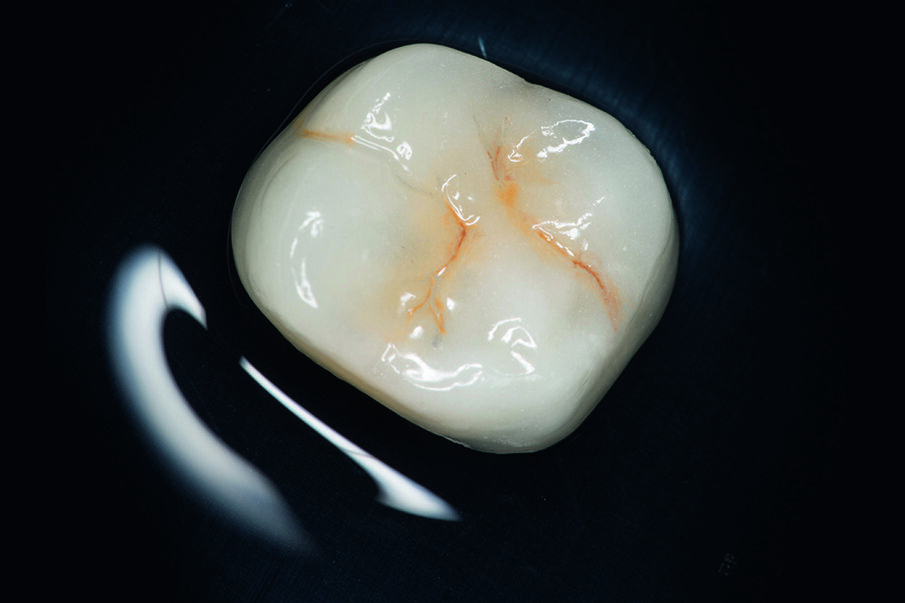

Fig. 8: The ceramic crown was etched with hydrofluoric acid.